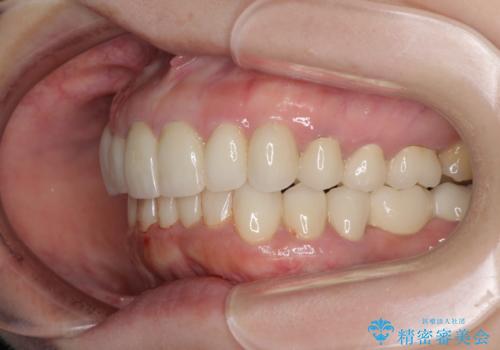

期間と費用はかかりましたが、気になっていた部分全てを改善でき、患者様には大変満足していただきました。